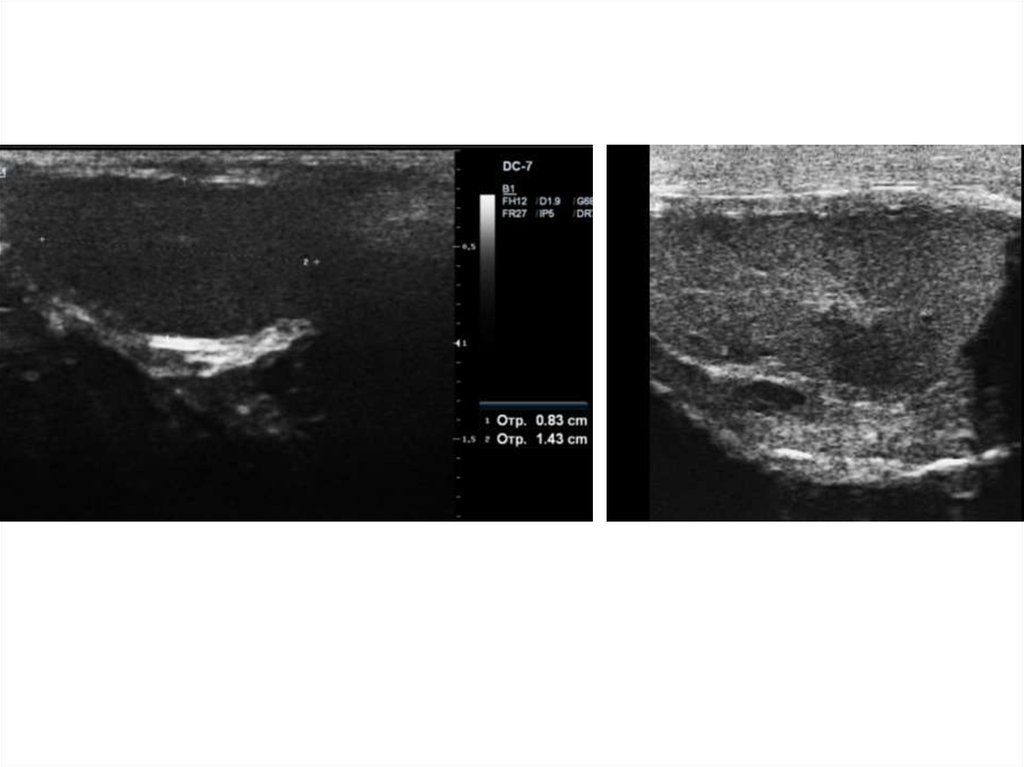

Гипоэхогенное НО Продольно и поперечно

НО кавернозное